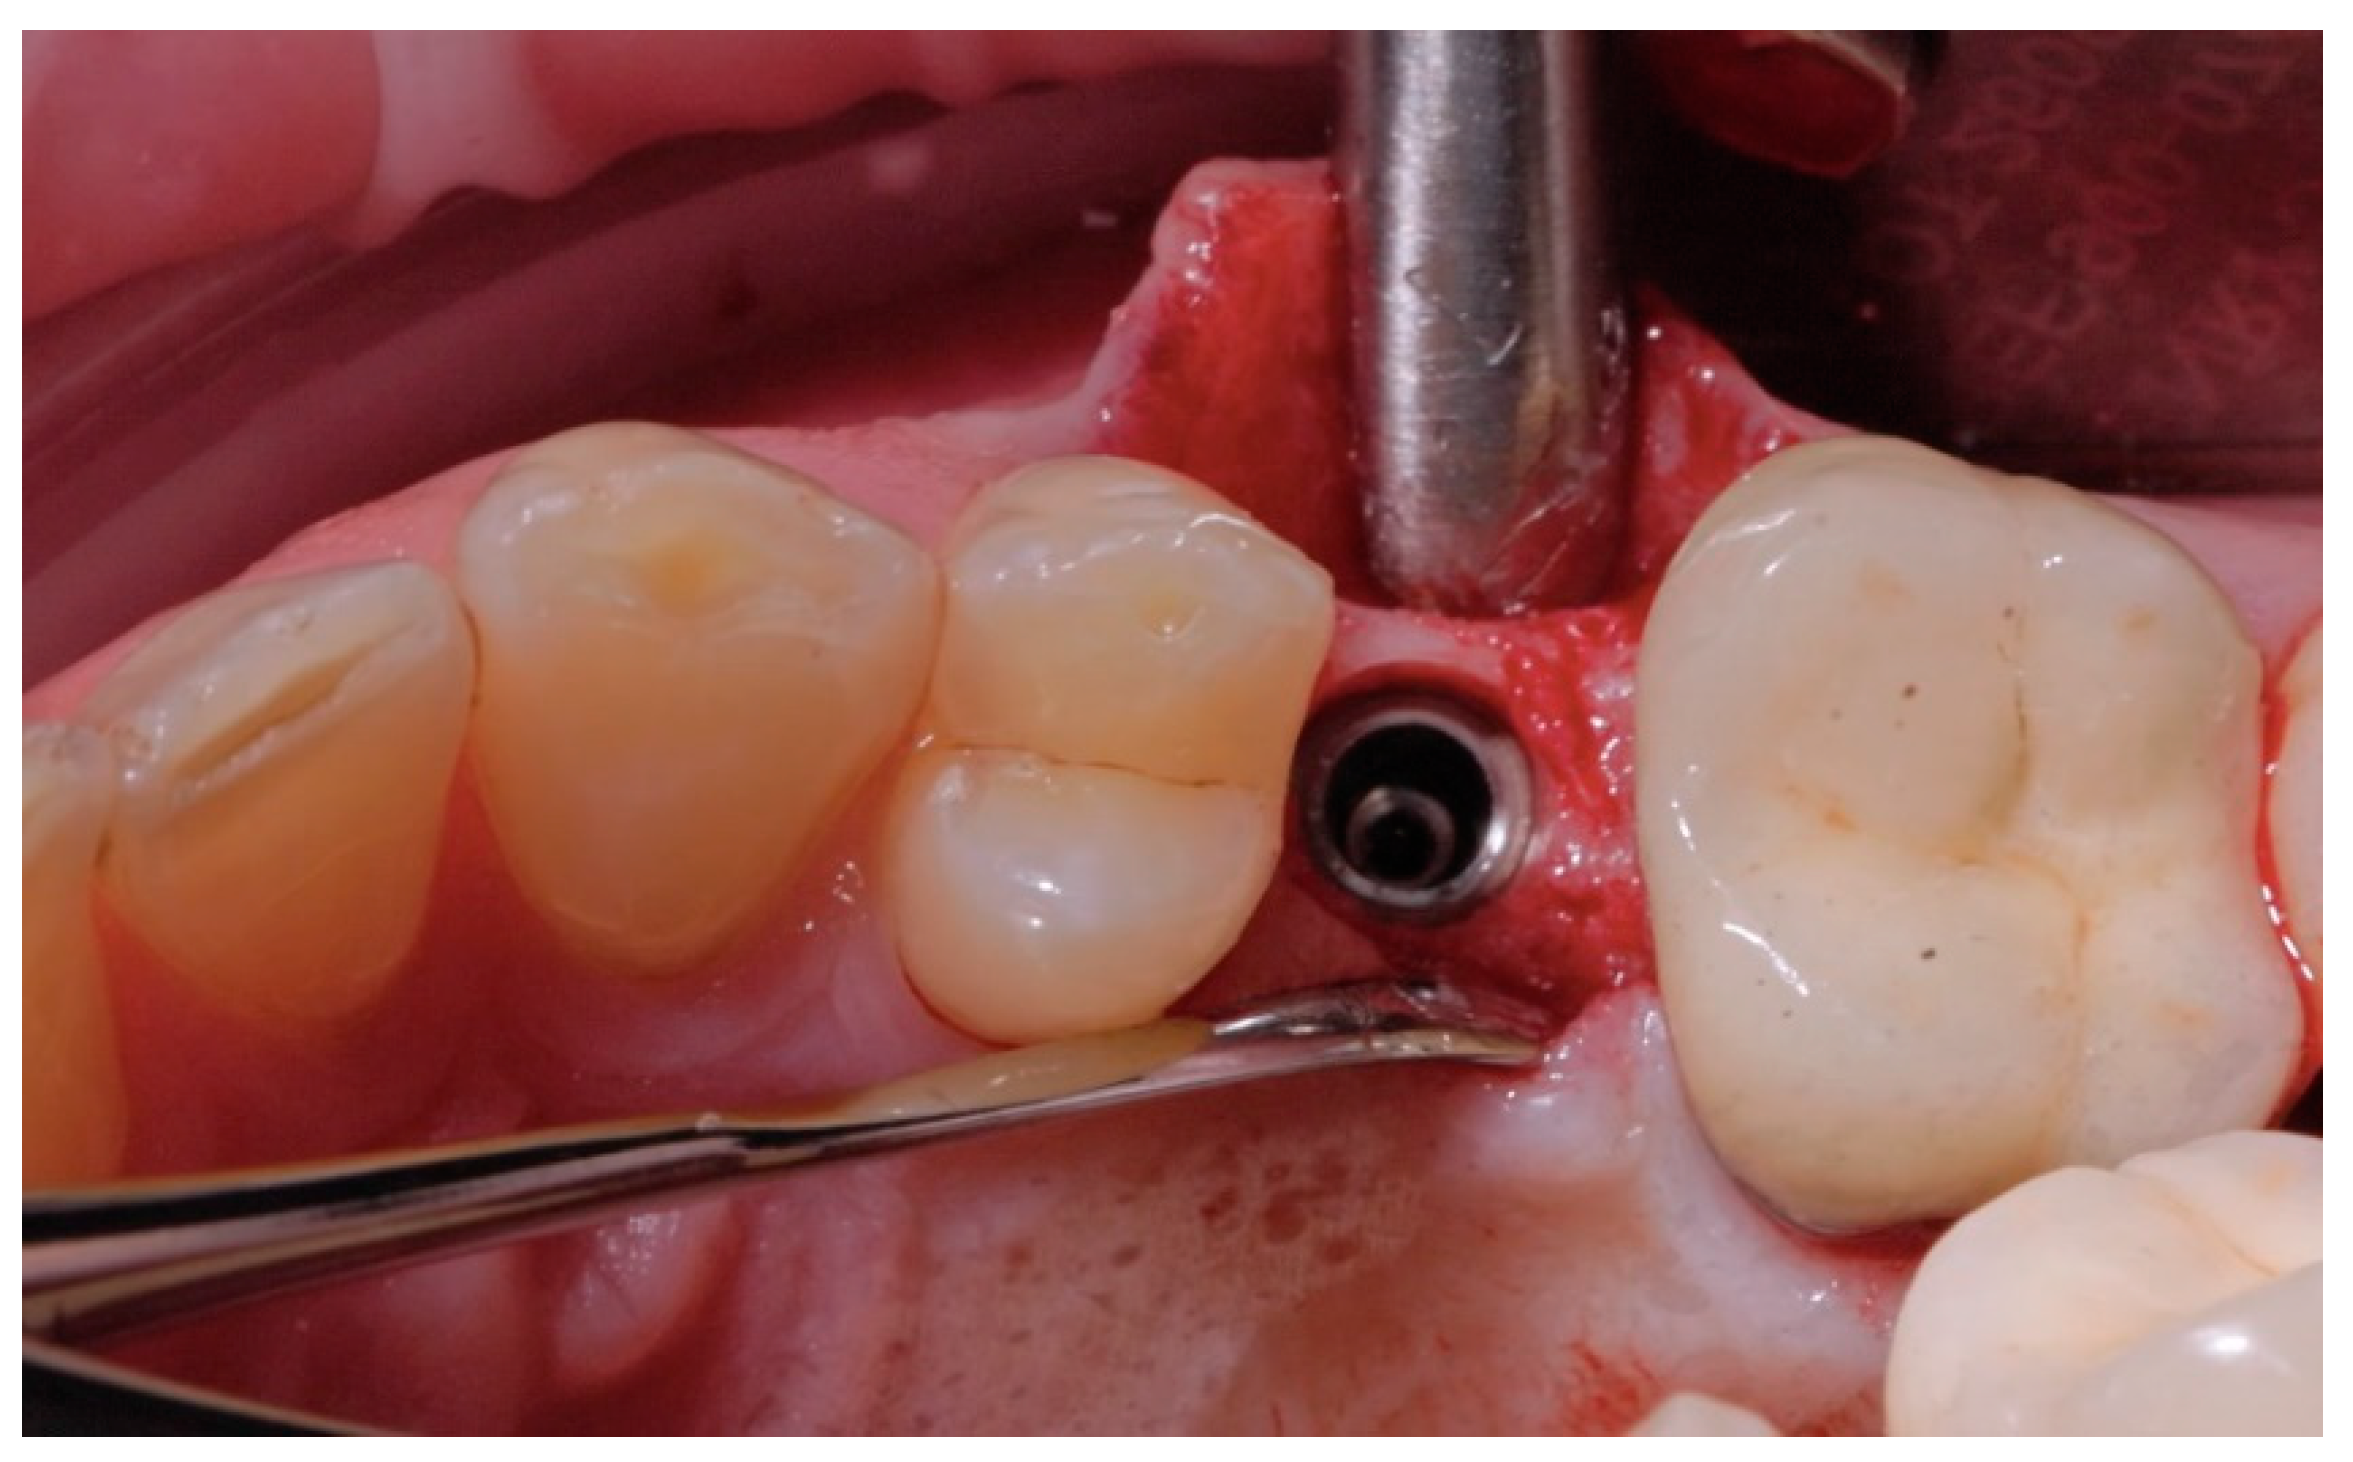

2.2. Surgical Procedures

2.3. Prosthetic Protocol